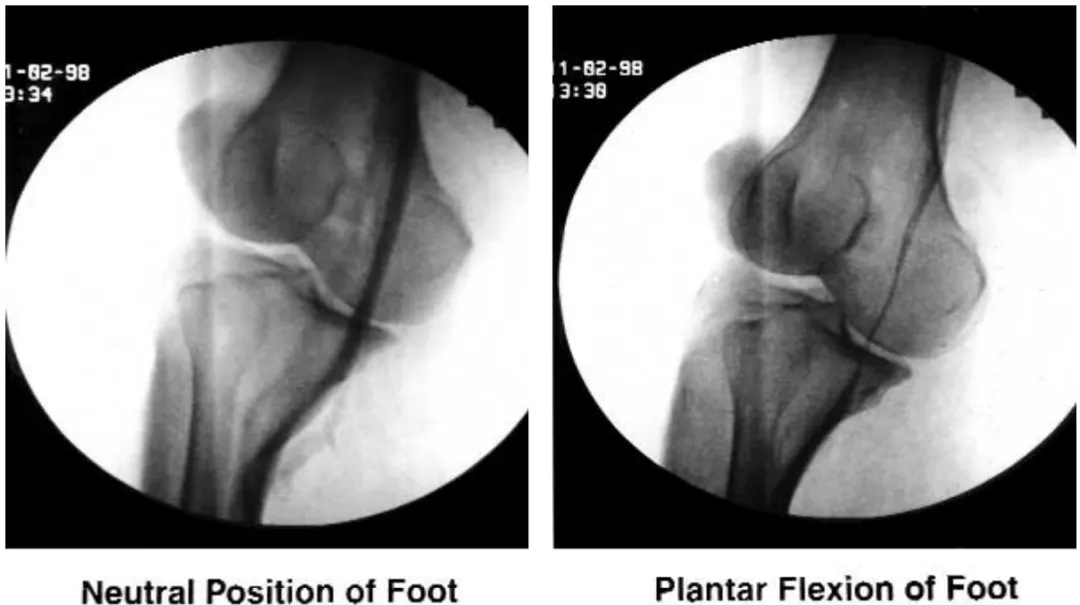

在膝关节伸展时,约 25%的人中,腘静脉可能会被腓肠肌压缩。有时会导致症状,被称为腘静脉卡压综合征 (popliteal vessels entrapment syndrome, PVES)。患有这种综合征的患者可能出现水肿,有时在受影响的侧出现深静脉血栓。其治疗方法包括弹力袜,对于更严重的病例,则保留手术减压。

在踝关节处将脚向下弯曲的动作,即脚底向下弯曲时,常规上行静脉造影中可见腘静脉卡压。